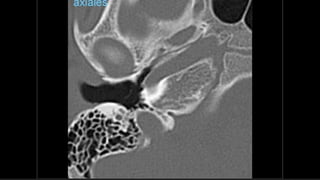

Evaluación Imagenologica

• #38 Izqu. AXIAL-- fxLongitudinal perdonan la capsula otica (laberinto oseo) Centro AXIAL fx trnasversa lascuales tperdonan el lab erinto oseo Dere: MIXTA – tmp perdona

• #52 AXIAL Frctua canal carotideo